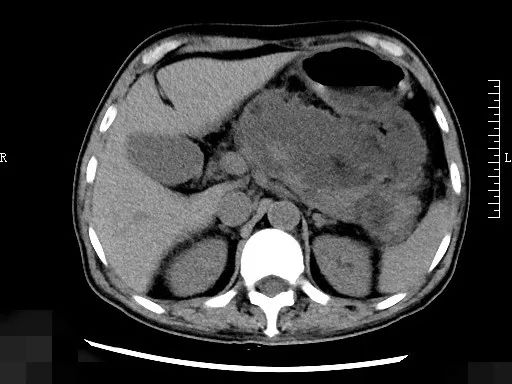

患者是名60多岁的周大叔(化名),1月前因重症胰腺炎在当地医院诊治,目前发热,体温最高39℃。急诊行CT显示胰腺周围一个14X8cm的脓腔,诊断为“胰腺坏死性包裹并感染”。由于脓腔巨大,对周围脏器压迫明显,且感染通过使用高级抗生素不能缓解,患者每天的体温还是波动在38.5℃以上,每天的血糖需要依靠泵入胰岛素才能降低到10mmol/L以下,血象、CRP这些炎性指标都居高不下。

经过讨论以及征求家属意愿,决定实施超声内镜引导下胰腺脓肿引流并支架植入手术,在麻醉团队的保驾护航下,手术顺利进行,术中用超声内镜经胃壁穿刺胰腺脓肿并扩张穿刺口,沿穿刺点电切造瘘,球囊扩张进一步扩大引流瘘道后,放置2根塑料支架,支架一端在胰腺脓肿腔内,一端在胃腔内,实现脓液持续向胃内引流继而经肠道排出,再放置1根鼻囊肿管,将脓液向体外引流。

术后当天患者体温即恢复正常,第二天行腹部CT检查,脓腔较前明显缩小。术后5天再次为患者实施了内镜下胰腺脓腔的清创术,“这也是我第一次直面胰腺炎后坏死性包裹的脓腔,就像是一个淤泥坑。”主管医师沈洁说,术中使用内镜深入脓腔将患者的“淤泥”一点点的游离,通过内镜取出。二次手术后患者体温、炎症指标均恢复正常。